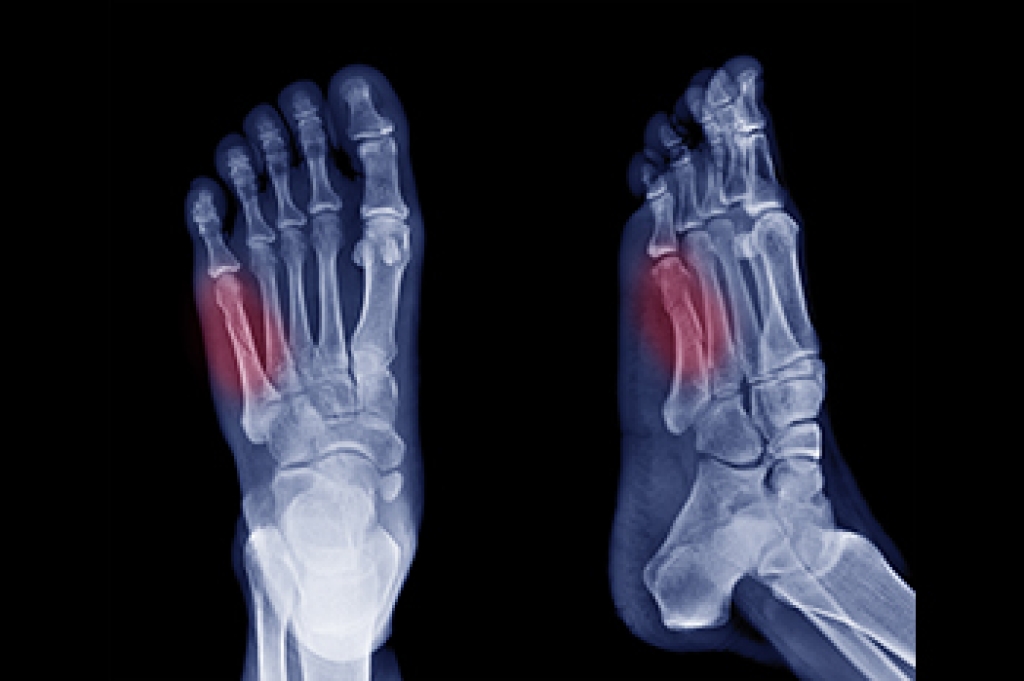

A Jones fracture refers to a break or crack in the fifth metatarsal bone, located on the outer side of the foot near the ankle. Symptoms typically include pain, swelling, bruising, tenderness on the outer part of the foot, and difficulty walking. Diagnosis usually involves a visit to a podiatrist, who will perform a physical examination, review the symptoms, and take a detailed medical history. To confirm the fracture, imaging tests like X-rays are commonly used. Treatment options depend on the severity of the fracture. For minor cases, rest, mild pain relievers, and possibly a cast or splint may be recommended. Crutches could also be necessary to help avoid putting weight on the affected foot. In more severe cases, surgery may be required to properly heal the bone. Full recovery can take several months, so it is important to allow enough time for the bone to heal completely to prevent further injury. If you suspect you have a Jones fracture, it is suggested that you consult a podiatrist for an accurate diagnosis and personalized treatment plan.

A broken foot is caused by one of the bones in the foot typically breaking when bended, crushed, or stretched beyond its natural capabilities. Usually the location of the fracture indicates how the break occurred, whether it was through an object, fall, or any other type of injury.

Treatment for broken bones varies depending on the cause, severity and location. Some will require the use of splints, casts or crutches while others could even involve surgery to repair the broken bones. Personal care includes the use of ice and keeping the foot stabilized and elevated.